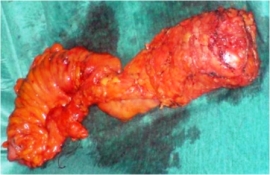

Εισαγωγή Οι αρχές που διέπουν τη θεραπευτική στρατηγική του καρκίνου του ορθού διαφέρουν σημαντικά από αυτές που ακολουθούνται στην αντιμετώπιση του υπόλοιπου παχέος εντέρου. Στόχοι της χειρουργικής θεραπείας του καρκίνου του ορθού, η οποία και αποτελεί το βασικό μέσο εκρίζωσης του εν λόγω όγκου και επίτευξης μακράς επιβίωσης των ασθενών,…